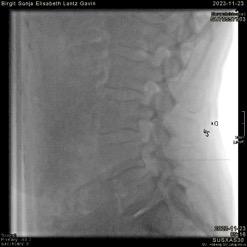

reduceras en hel del utan påverkan på bildkvaliteten eftersom skelett har en hög inneboende kontrast visavi omgivande mjukdelar. Det är fullt möjligt att göra CT till samma organdos som för röntgenundersökning, till exempel ländrygg2 vilket ger en CT av förhållandevis låg kvalitet med hög brusnivå, men som ändå ger mera diagnostisk information än motsvarande röntgenundersökning tack vare den tomografiska metoden och tredimensionell datavolym. Det kan dock krävas en del justeringar av inställningar för att få en så bra lågdosundersökning som möjligt. Bild 3.

Bild 3. Lågdos-CT av en äldre patient med långdragen ankyloserande spondylit med ankylos i kotpelare och sacroiliacaleder. Sagittal reformatering och 3D-rekonstruktion. Bild 4. Cone-beam-CT med stol för patienten och vinklat gantry. Foto Mats Geijer.